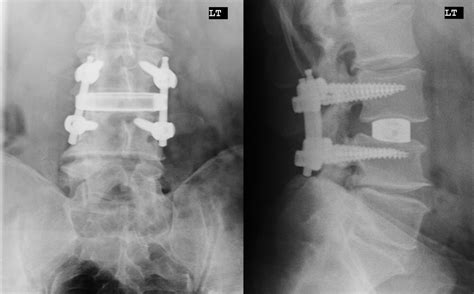

• Spondylolisthesis: A condition where one vertebra slips forward over another. If the slippage is severe or causes persistent pain and nerve compression that doesn't respond to conservative care, fusion is often indicated.

• Degenerative Disc Disease (DDD): While not all DDD requires surgery, severe cases where the disc has collapsed to the point of causing chronic, debilitating pain and spinal instability may require a fusion to restore structural support.

• Spinal Stenosis: In cases where stenosis is accompanied by significant instability, a decompression surgery (like a laminectomy) might be paired with a fusion to prevent further slippage.

To determine when is spinal fusion necessary, a spine surgeon relies on a combination of imaging and physical testing. MRI scans are used to visualize soft tissue, including discs and nerves, while X-rays—specifically "flexion-extension" X-rays—are crucial for assessing spinal stability. During these X-rays, the patient is asked to bend forward and backward to see if the vertebrae move more than they should, which is a hallmark sign of instability.